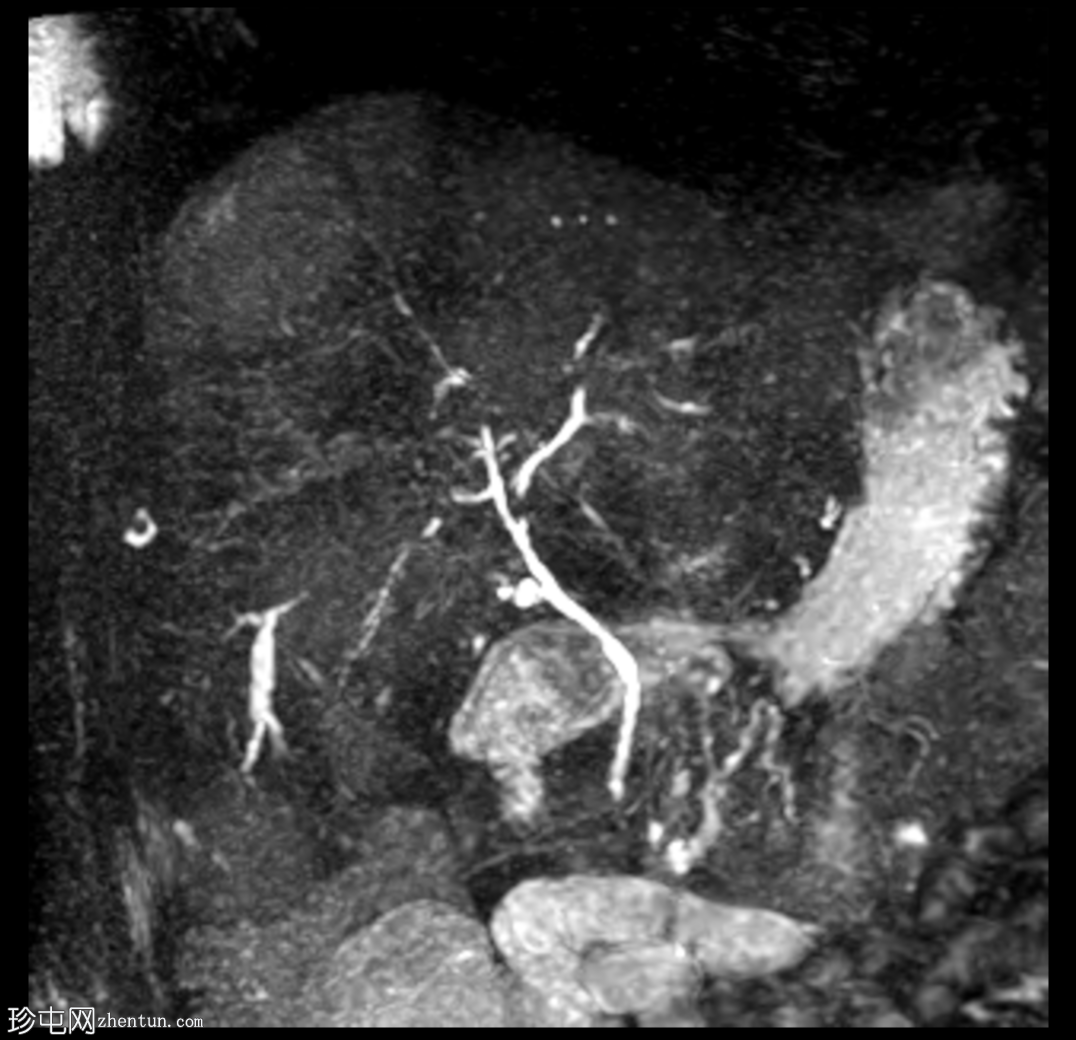

冠状位

MRCP

MIP、MRCP

磁共振胰胆管造影(MRCP)显示肝转移灶处存在多处短段胆管狭窄和闭塞,上游胆管扩张,提示

肿瘤

直接压迫/浸润。

肝总管(CHD)和胆总管(CBD)通畅,管径正常。

无胆总管结石。

与转移性胆管癌相比,恶性胆道梗阻在胆管癌中更为常见。